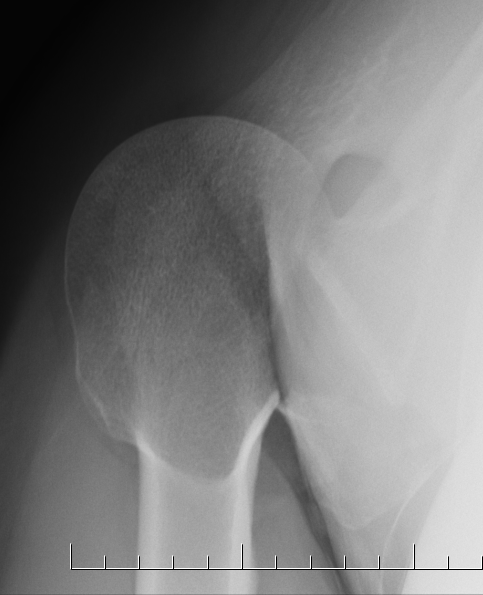

- frequently missed on xray

- sensitivity of xray 16%